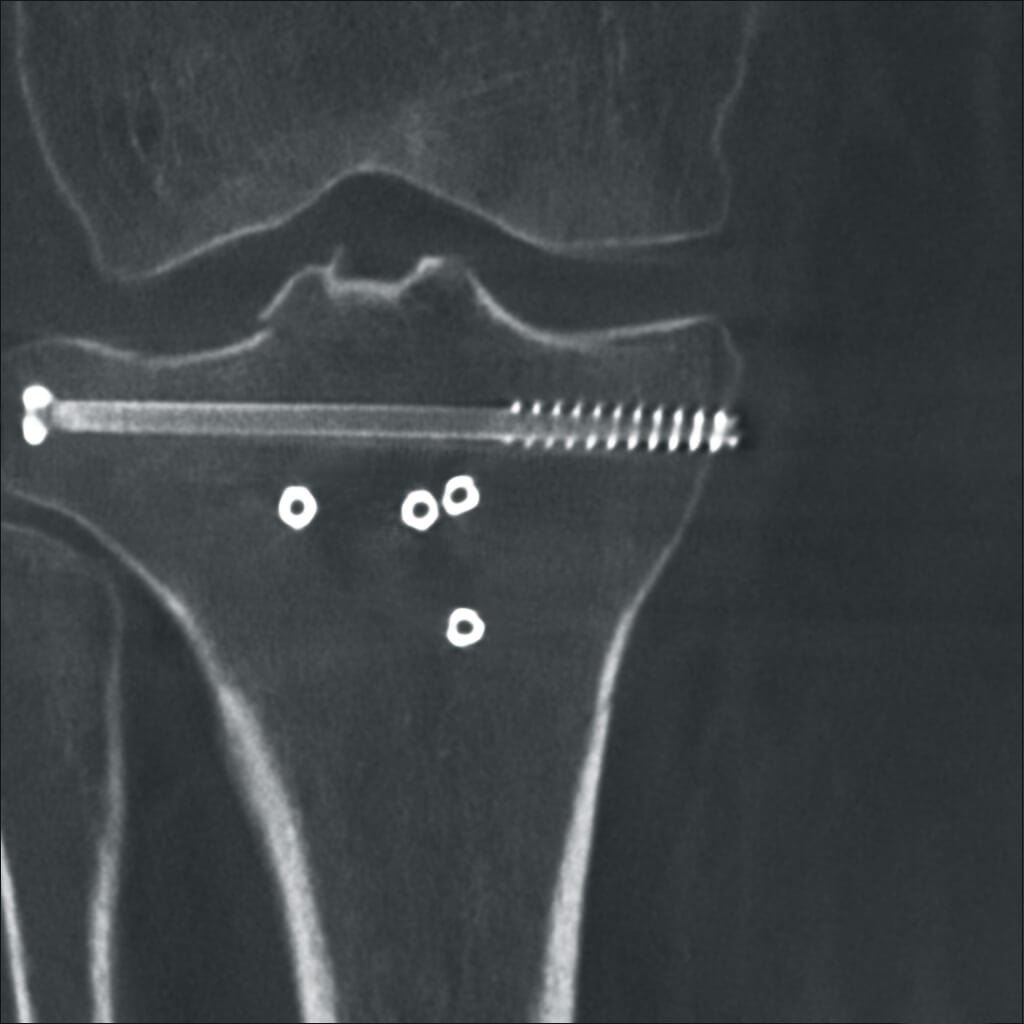

Высокая детализация для сложных операций

Полное отсутствие искажений снимков в сочетании с высоким динамическим диапазоном широко востребованы как при сложных операциях в нейрохирургии, сосудистой хирургии, инвазивной радиологии, так и в гибридных областях применения, а также в ортопедии, травматологии. В сосудистой хирургии особенно важны высокий динамический диапазон и пространственное разрешение, обеспечивающие детальную визуализацию даже мельчайших сосудов. Специализированное программное обеспечение SmartVascular позволяет проводить настройку системы для васкулярных операций и сосудистой хирургии.

Точная визуализация анатомических деталей, мягких тканей и костных структур обеспечивается за счет светочувствительной матрицы 3kх3k пикселей с высоким динамическим диапазоном.

Автораспознавание металла

Винты, пластины, импланты и хирургические инструменты автоматически распознаются при попадании в видимое поле аппарата. В этом случае происходит корректировка мощности дозы облучения для улучшения качества снимка.